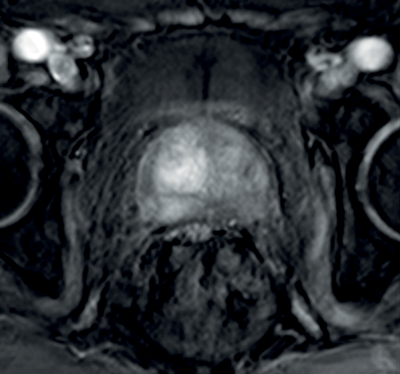

In prostate cancer, DCE MR follows the characteristic pattern of malignant enhancement with early, intense enhancement and rapid wash-out. It is most often correlated with T2-weighted and diffusion-weighted sequences for greater accuracy in detection (Figure 3).

Figure 3a: DCE image of the same patient as Figure 2 showing

avid enhancement in the right central zone tumour.

Figure 3b: T2WI showing tumour at the right apex.

Figure 3c: Avid enhancement seen within the tumour.